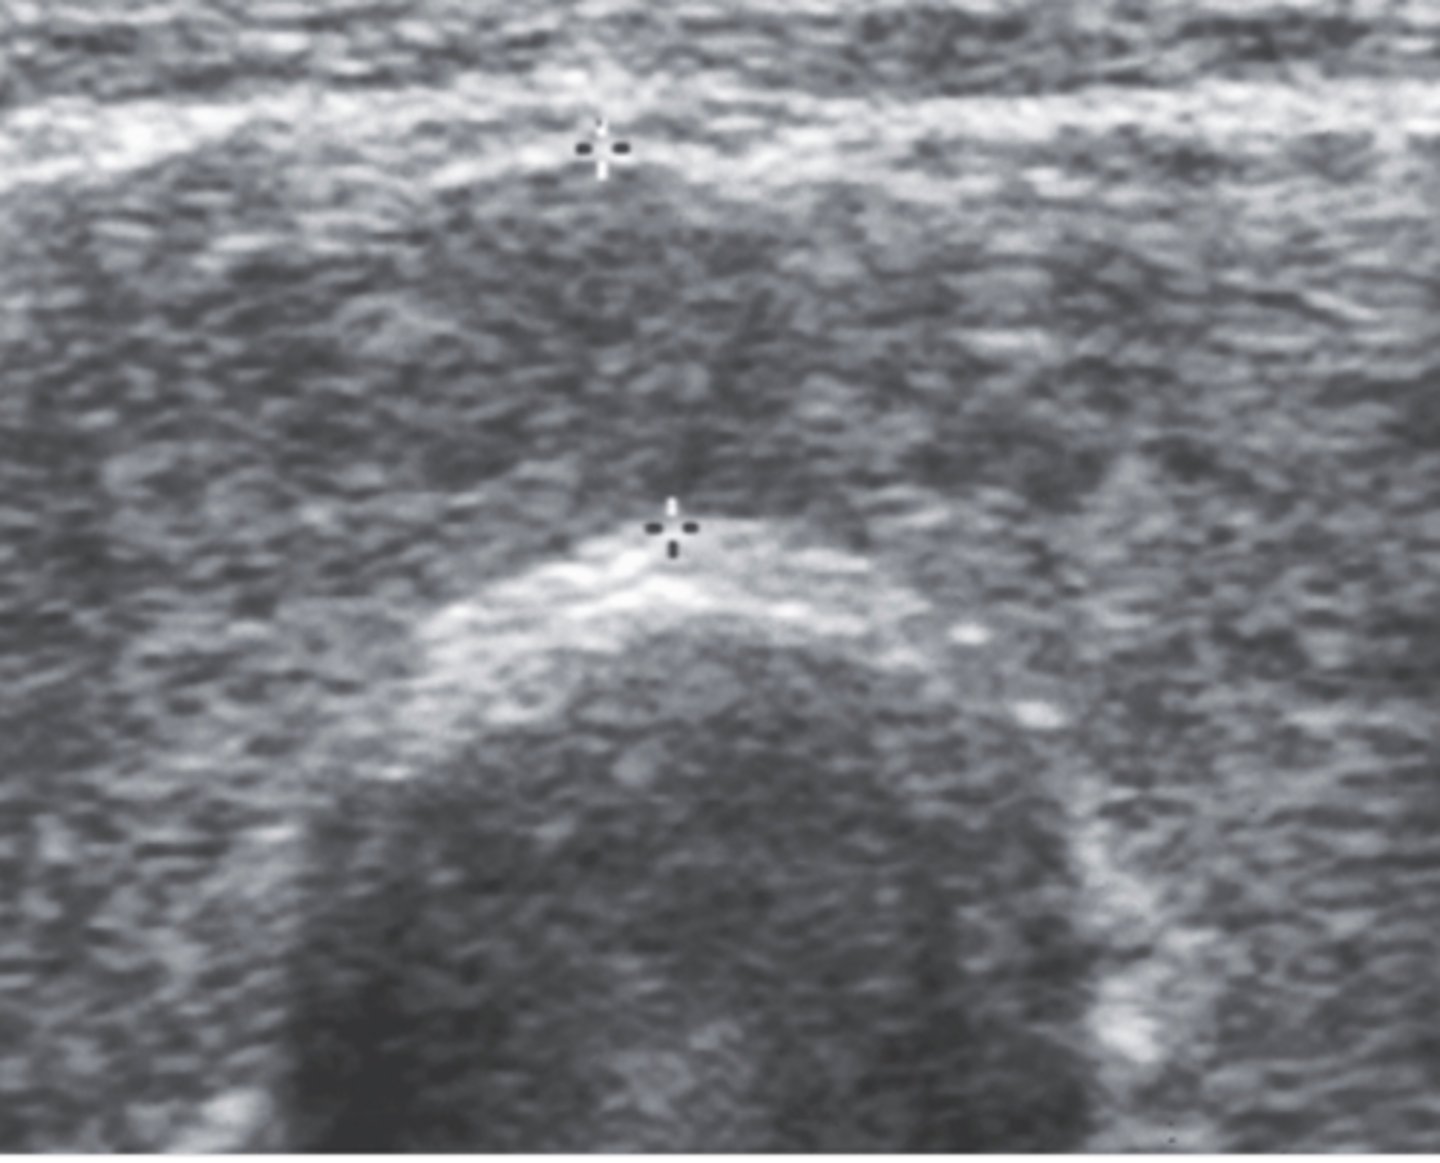

7. The transverse mid-neck image in Figure 12-24 is depicting a measurement that should not exceed:

a. 5 mm

b. 10 mm

c. 3 mm

d. 15 mm